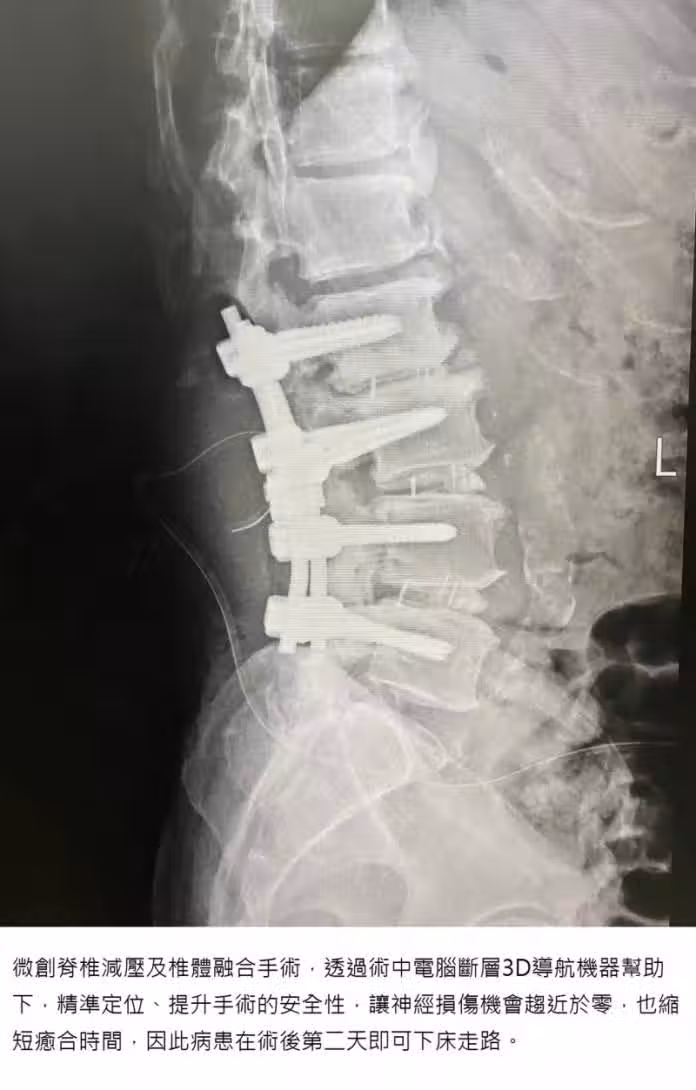

但現在的新型微創脊椎減壓及椎體融合手術,是在術中電腦斷層3D導航機器幫助下,能精準定位、提升手術的安全性,讓神經損傷機會趨近於零,也縮短癒合時間,因此病患在術後第2天即可下床走路!